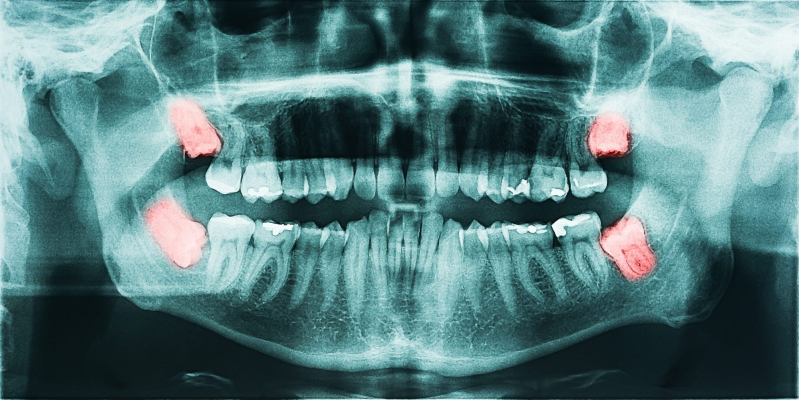

When a wisdom tooth cannot fully come in, it is called an impacted wisdom tooth. This can lead to repeated infections and discomfort.

A simple exam and X-ray can usually tell if removal is necessary.